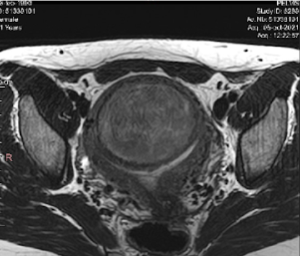

- El tamaño y localización de los miomas (ver clasificación de la FIGO)

De hecho, todos los miomas del 0 al 6, son candidatos a la Radiofrecuencia.

- Compresión vesical y rectal, provocando micciones constantes o tenesmo rectal por compresión del mioma.

- Aumento del volumen abdominal, a veces con compresión de otros órganos.